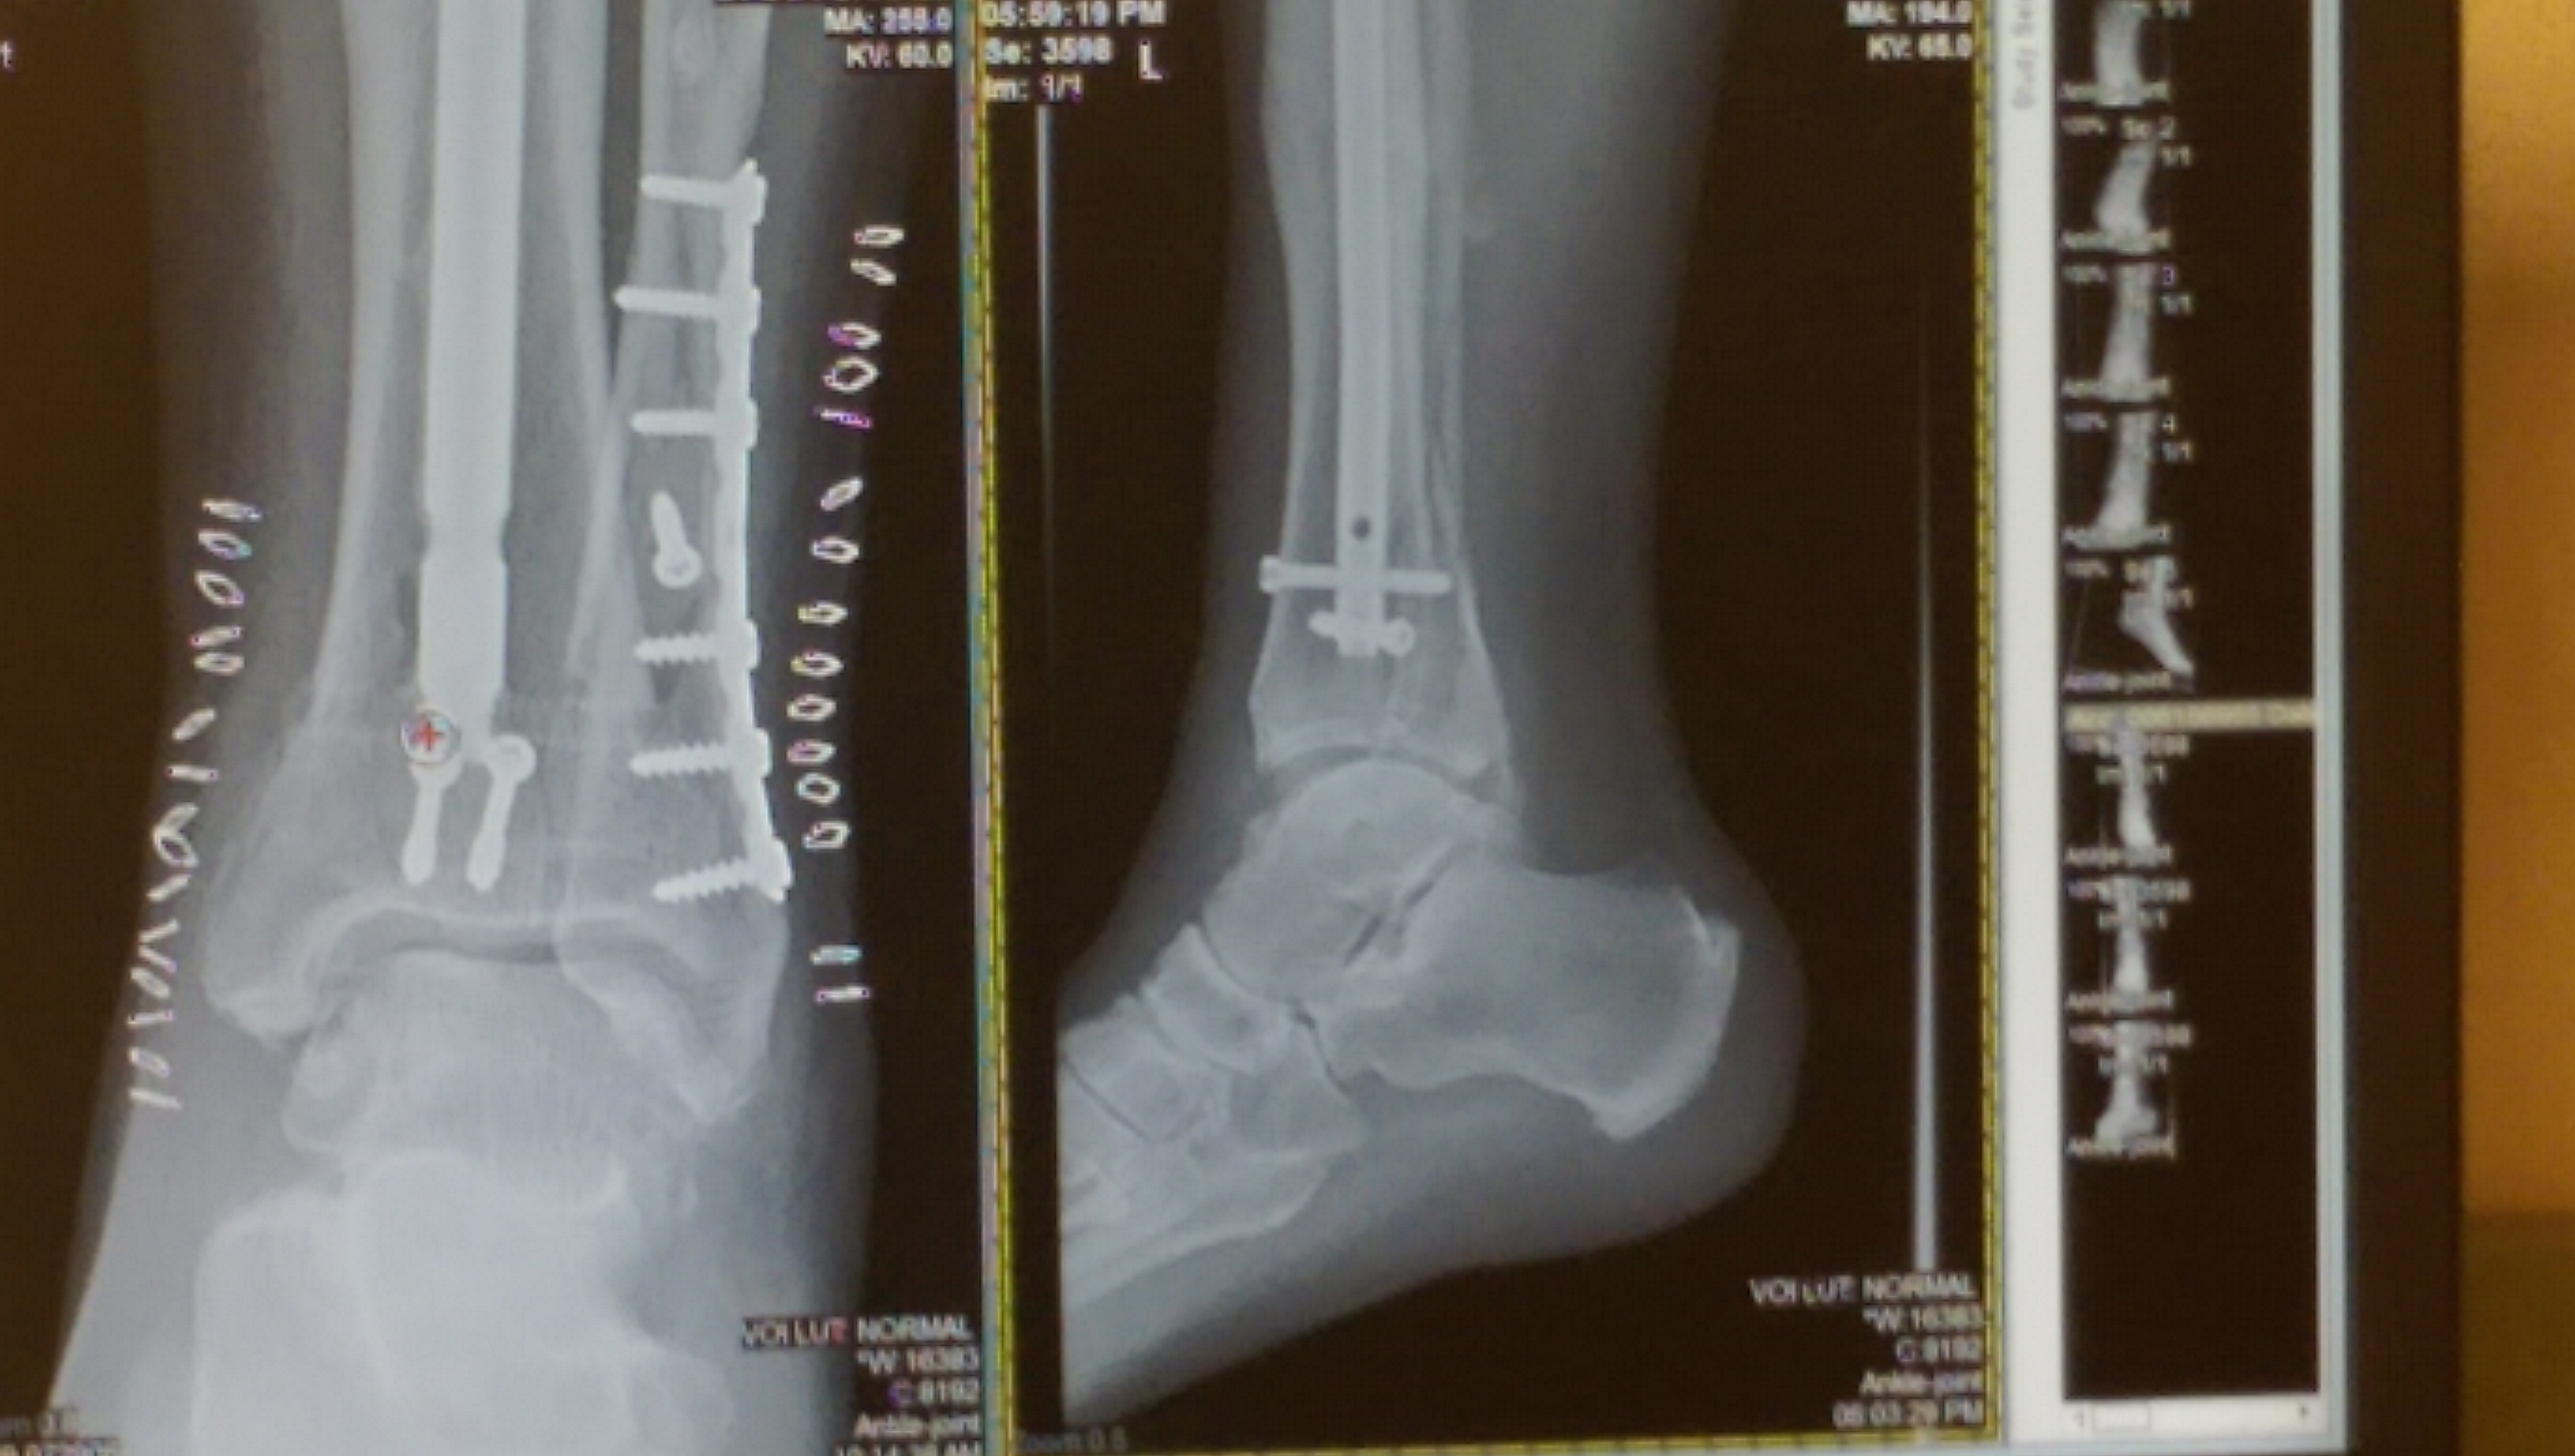

This is the same leg I broke in 2009 in 7 places and this time I broke the fibula cracked the tibular and broke the ankle I screamed like a 10 year old girl lol.

I had a cat scan done yesterday and went to doctor for results and he said the ankle has broke into and will need surgery Thursday he is going to take out 1 screw from the last surgery I had on this leg and put a plate in and 4 more screws.

Doctor said it was broken worse than first thought and had to use 9 screws and a plate to get the bones back together.